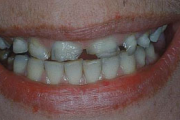

Turritavad ülemised lõikehambad.